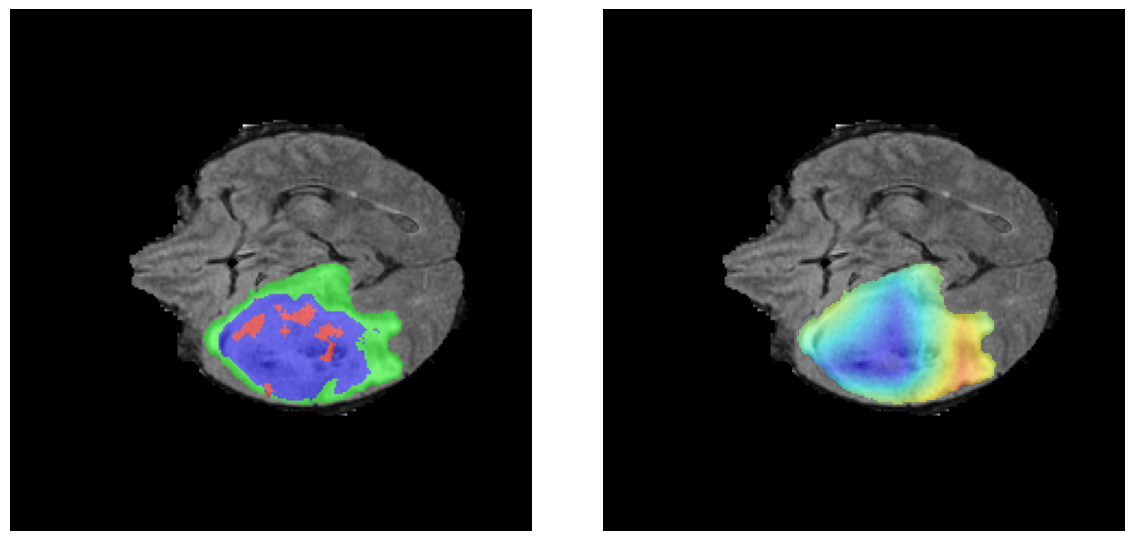

Mapas de Explicabilidad (Grad-CAM++)

Visualización de las regiones de atención del modelo que validan su razonamiento clínicamente relevante

Ejemplos HGG - Atención en Núcleo Necrótico y Tumor Realzado

HGG Grad-CAM++ 1 HGG Grad-CAM++ 2 HGG Grad-CAM++ 3 HGG Grad-CAM++ 4 HGG Grad-CAM++ 5 HGG Grad-CAM++ 6

Los heatmaps muestran que el modelo concentra su atención en las regiones de Tumor Realzado (rojo) y Núcleo Necrótico (azul), características patológicas clave de los gliomas de alto grado.

El análisis Grad-CAM++ reveló que el modelo desarrolla automáticamente la capacidad de localizar las regiones tumorales. Para casos HGG, la atención se alinea fuertemente con las regiones de Tumor Realzado (ET) y Núcleo Necrótico (NCR). En contraste, los casos LGG muestran atención más difusa, principalmente concentrada en la región de Edema Peritumoral (ED), lo cual es consistente con la patofisiología conocida de los gliomas.

El modelo, entrenado únicamente con etiquetas de clasificación a nivel de imagen (HGG/LGG), desarrolló automáticamente la capacidad de localizar las regiones tumorales sin supervisión explícita de segmentación. Este es un hallazgo significativo que demuestra capacidades emergentes del deep learning.

✅ Razonamiento Clínicamente Coherente